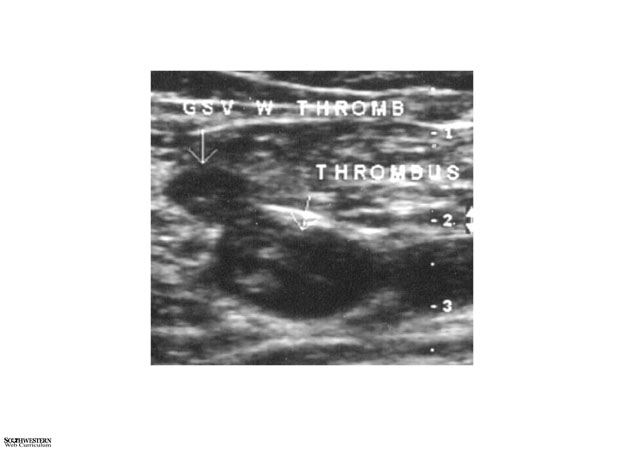

Sonographic scan showing clot in vein